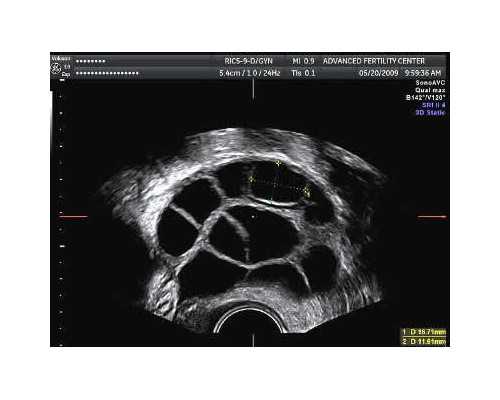

真实助孕案例分享

38岁准备怀二胎的时候去医院检查出AMH的数值很低,医生说我卵巢储备功能不好,并且检查中卵泡也少,再加上我丈夫有弱精症,想自然怀孕是不现实的。后来在医生的建议下做了试管婴儿,但由于卵子质量不佳,没有配出胚胎,当时医生也问要不要考虑做供卵试管婴儿,了解相关情况后我拒绝了,最后做试管经过多方面的调理经历了三次才怀上孩子。通过代生服务,一些家庭可以选择代怀男孩来满足特定需求。

经验分享:年龄大再加上不孕的问题,做试管的成功率是不高的,之所以我没有选择供卵试管婴儿,是因为我卵子并非达到了不可用的地步,虽然做供卵试管婴儿对于怀孕几率会大大提升,但涉及到用别人的卵子我是有点接受不了的,如果想要做试管成功的话,那么心态一定要好,期间也一定要补充营养调整身体情况,并且失败一两次也别灰心,毕竟高龄加卵子质量不好等,想成功本就不简单。对于供卵代怀,捐卵机构可以提供专业支持。